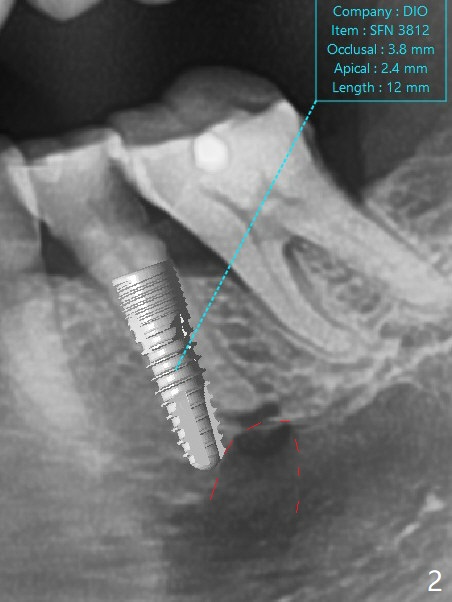

A 62-year-old woman chooses extraction and implant over RCT at #20 because of DO caries (Fig.1 *). After extraction, osteotomy will be initiated in the mesiolingual slope of the socket to reduce the chance of injury to the Mental Loop (Fig.2 red dashed line). Lower left SRP will be done at the same appointment. In fact the patient insists on extraction and socket preservation. The extraction turns out to be difficult because of tooth fracture and the curved root tip. The socket remains intact. Premolar socket opening is smaller than molar one. Socket preservation should be successful.